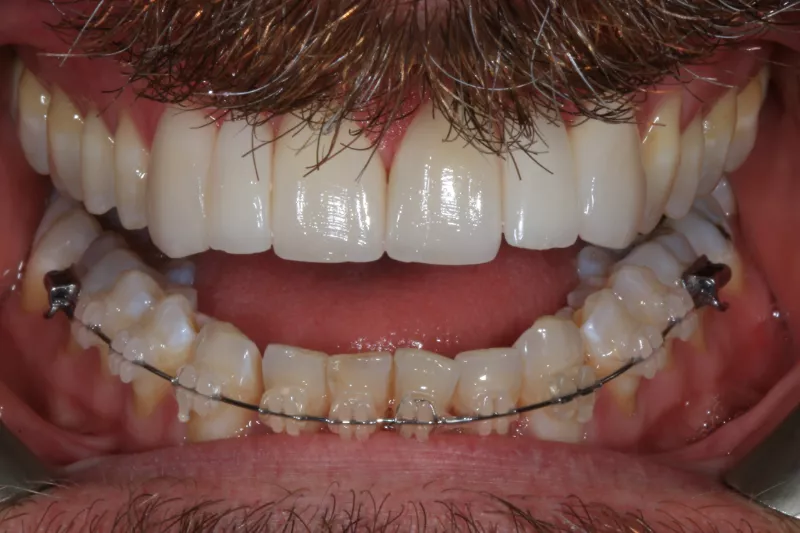

Fixed Ceramic Braces and At Home Teeth Whitening